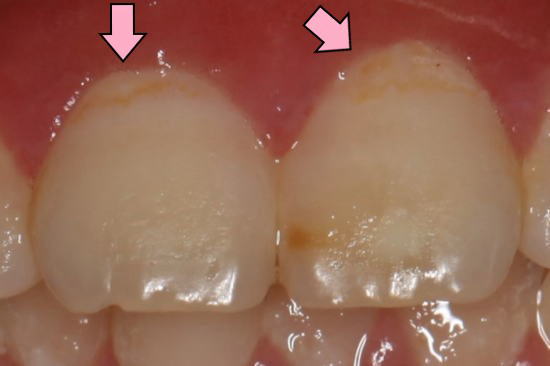

前歯の拡大: 矢印の所がむし歯(白濁)が進行している。 |

| 2015年12月14日:フッ素洗口開始して約4ヶ月半後 |

矢印の部分のむし歯(白濁)がなくなり、むし歯が消失(再石灰化)して きているのがわかります。 |